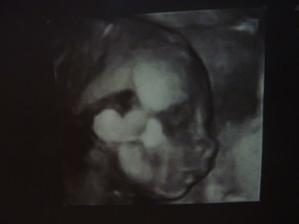

Prekvapkoo 🙂

Je to az neskutočne, ked som objavila tieto stránky, mali sme tesne pred svadbou, trávila som čas na mojasvadba.sk, po svadbe sme začali rekonštruovat, tak som sa nalepila na modrastrecha.sk. a vyše mesiaca už chodim na modrého konika až sa to asi na mna nalepilo a minulý týždeň som ostala prekvapená z //. Tak tu už nalepená asi aj ostanem 🙂))